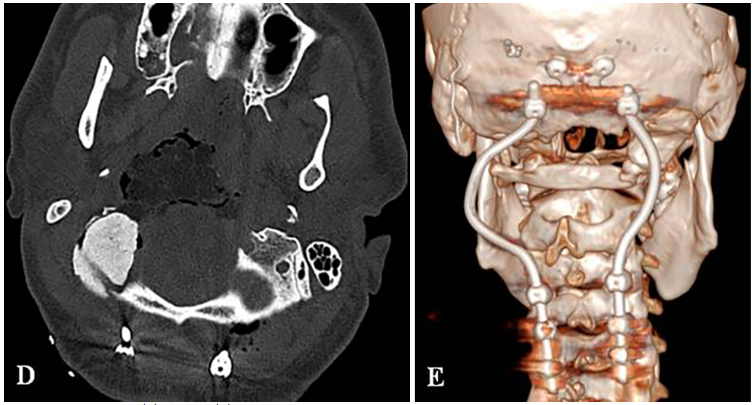

一名26岁男性患者,临床表现为颈部疼痛、严重吞咽障碍及双侧舌下神经麻痹(右侧完全性麻痹伴发舌肌萎缩,左侧为部分麻痹)。MRI与CT影像学检查结果显示,其颅颈交界区存在一直径达10厘米、体积约96.5立方厘米的巨大脊索瘤。该肿瘤呈浸润性生长,广泛侵犯右侧结构,累及范围包括椎前间隙、下斜坡、双侧枕骨髁、第一颈椎(C1)前弓以及第二颈椎(C2)齿状突。巨大肿瘤已导致脑干受压及双侧椎动脉移位,并向硬膜内扩张。

术前MRI与CT影像分别揭示了肿瘤的巨大范围及其对斜坡-枕骨髁造成的溶骨性破坏。主刀团队评估认为,肿瘤已对颅颈交界区骨质结构造成广泛侵蚀,术后极有可能出现颅颈不稳定。因此,手术方案确定为经远外侧经髁入路,施行显微镜与神经内镜双镜联合肿瘤切除术,继而进行枕颈融合术(OCF)。

需要特别指出的是,固定根钉的曲线形横向弯曲设计,核心目的之一是为患者后续的质子治疗创造出一个无金属干扰的定位与治疗通道。术后CT与MRI复查证实肿瘤已达完全切除,病理学检查确认为典型脊索瘤。术后患者吞咽功能显著改善,颈部疼痛缓解。在恢复数周后,该患者顺利接受了质子治疗。